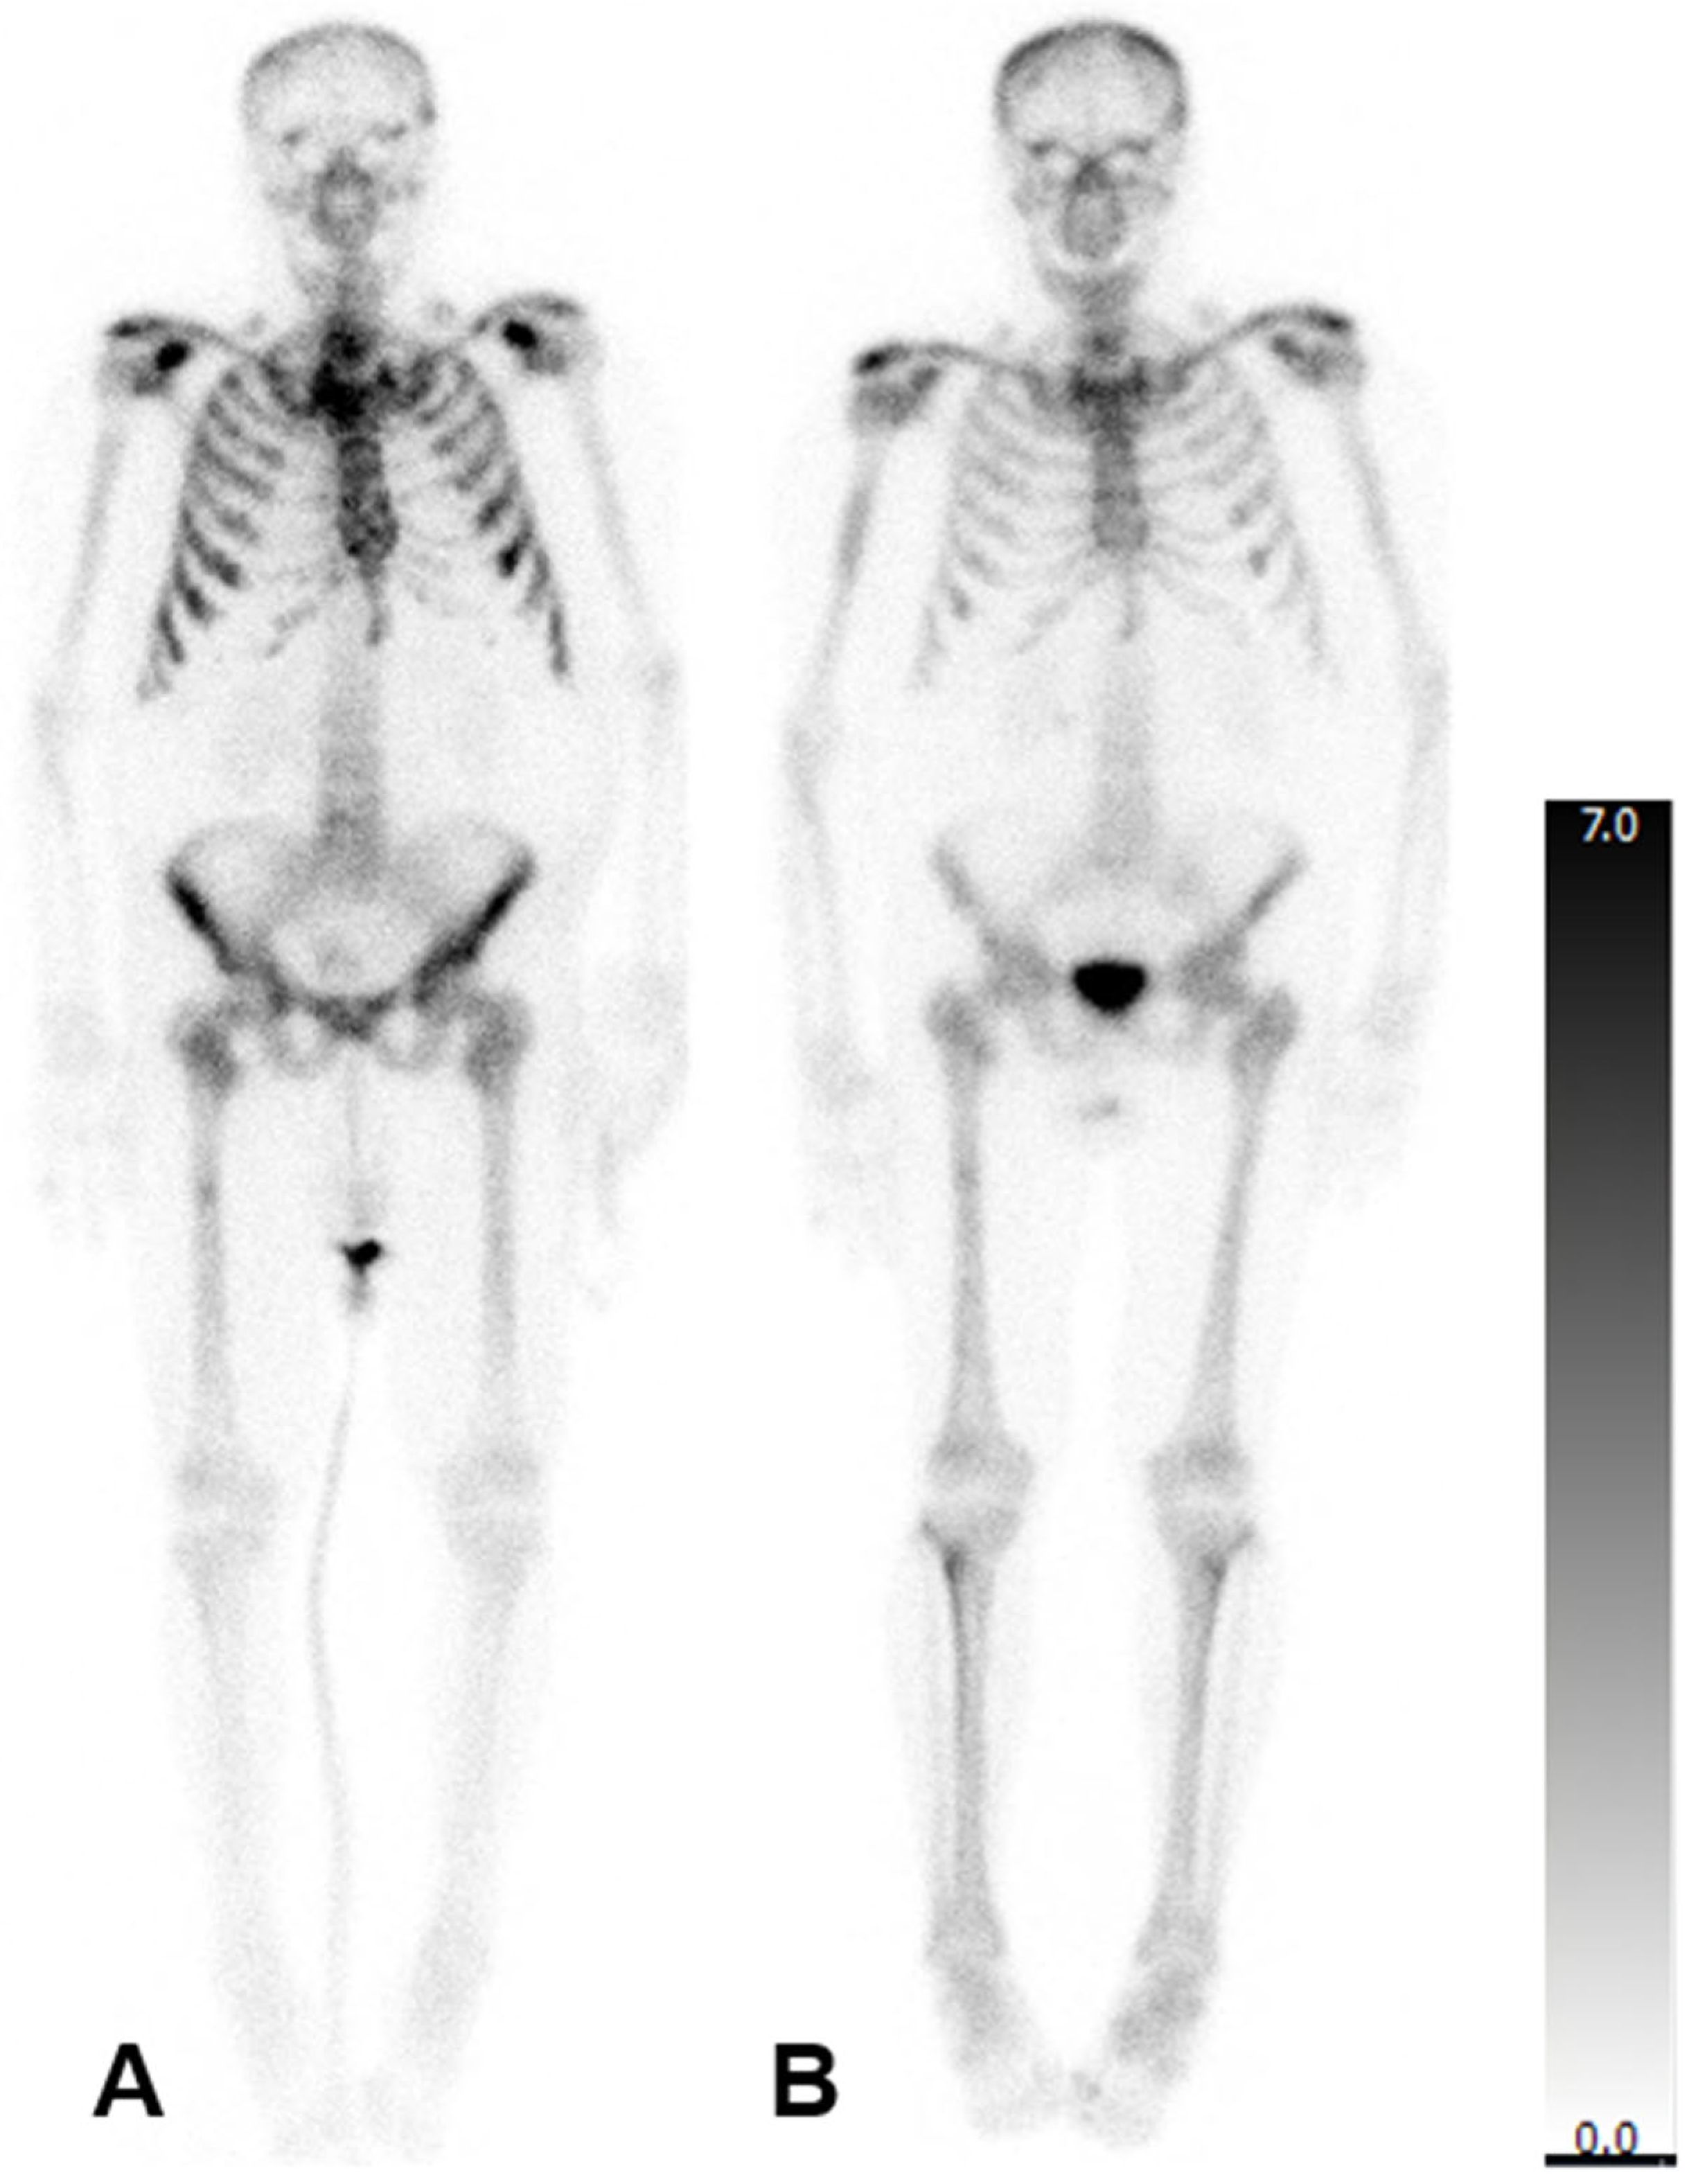

In patients who were administered six cycles, there was no significant change in the mean aBSI (2.6 ± 4.3%; before: 2.6 ± 3.3%; p = 0.247) or the mean TTV (208.8 ± 185.2 mL; before: 217.4 ± 175.8 mL; p = 0.784). However, the mean SUVmax reduced significantly (548.1 ± 342.2; before: 891.6 ± 539.6; p = 0.001). A representative patient case is illustrated in Figure 2.

Figure 2. Bone scintigraphy of an 83-year-old man with mCRPC. aBSI prior to 223Ra therapy was 7.8%, TTV was 549.32 mL, and SUVmax was 1500 (A). After six cycles of 223Ra therapy aBSI was 4.1%, TTV was 368.05 mL, and SUVmax was 1284 (B).